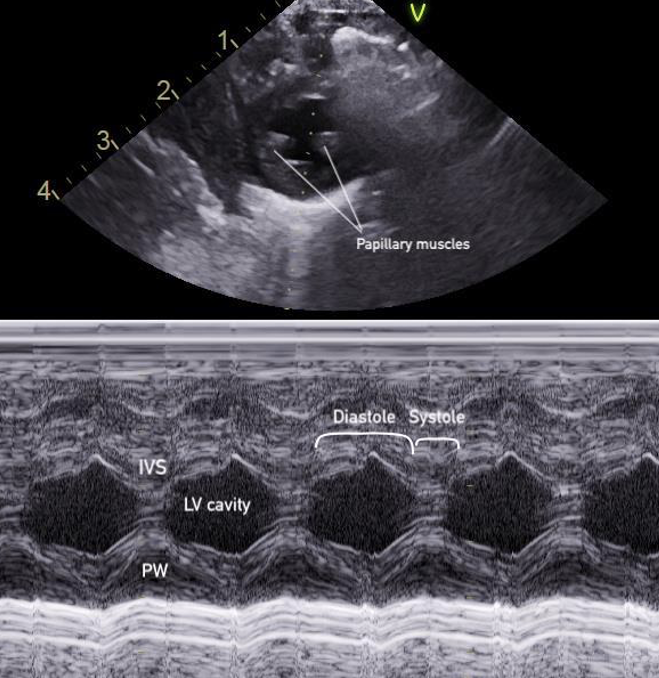

PSAX M-Mode

At the mid-papillary level, placing M-mode across the LV walls produces a motion trace of the septal and posterior walls throughout the cardiac cycle with distance displayed on the y-axis and time on the x-axis. The tracing shows the walls coming toward each other during systole and moving apart during diastole, with the LV cavity changing width in between (figure 15).

Figure 15: M-mode of the PSAX mid-papillary level

This pattern forms the basis for calculating fractional shortening (FS), which describes how much the LV diameter decreases during contraction, and linear EF, which measures volumetric change(figure 16). The FS and EF can be used to semi-quantify LVfx.

Measurements for FS and linear EF should be obtained at a single timepoint along the x axis corresponding to end-diastole and end-systole, rather than by selecting maximal wall excursion at different timepoints. Measuring the septum and posterior wall at different points of maximal excursion can result in inaccurate LV dimensions and overestimation of systolic function. It is also imperative to avoid placing the M-mode cursor through the papillary muscles, to ensure the true endocardial excursion is captured.

FS: percentage decrease in the LV diameter during contraction

Figure 16. LVIDd and LVIDs caliper placement for FS/EF calculation in PSAX M-mode

PSAX M-Mode Technique

1. At the mid-papillary level, place the M-mode curser perpendicularly through the centre of the LV cavity, between the papillary muscles

2. Measure the FS if findings appear grossly abnormal, when a quantitative baseline is useful for follow-up or clinical reassessment, or consultation with cardiology is anticipated.

– Select the FS calculation package and measure the left ventricular internal diameter in diastole (LVIDd) and in systole (LVIDs)

3. Save the M-mode image, and include the measurement if performed.

Note: FS M-mode can also be done in the PLAX view, by placing the M-mode cursor just past the MV leaflet tips; however, it is simpler and preferred in the PSAX view due to better alignment of the M-mode cursor perpendicular to the LV walls, which ensures more accurate and reproducible measurements.

What is Normal & Not Normal

- Normal values for FS in infants and children are typically between 28% and 46% [18,22] (figure 17).

- A FS <28% is generally considered abnormal. This can be further categorized into mild, moderate and severe systolic dysfunction (table 3) [22] (Figure 18).

- In pediatrics, normal EF is ≥ 55% (figure 17)[23].

Figure 17. PSAX M-mode normal FS and EF

Figure 18. PSAX M-mode abnormal FS